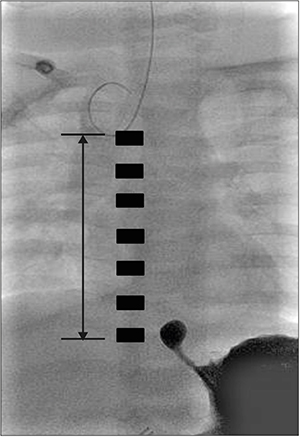

Seven months later, his body weight was 11.2 kg, and definite operation was planned. Since the distance measured via fluoroscopy between the upper and lower esophageal stumps was more than 6 vertebrae (i.e. too long to achieve primary end-to-end anastomosis), esophageal replacement with gastric tube (

Fig. 1) was performed.

Fig. 1 Fluoroscopy at the age of 7 months. Rudimentary distal esophagus, 6 vertebrae gap, distance from proximal to distal atresia: 8 cm.